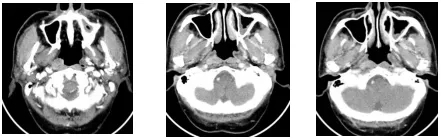

当时放疗医师勾画靶区时,参考了之前的PET-CT结果,将右侧鼻咽部高代谢病灶作为肿瘤靶区,从而有效避免邻近组织的不必要照射。体现了PET-CT协助放疗医师更精确的在细胞代谢水平上进行靶区勾画。患者进行12次放疗后,出现了严重的口腔粘膜反应,被迫停止放疗,并未完成根治剂量的照射。放疗后的影像评估显示:鼻咽部肿物明显减小,只是在粘膜上还有少许存在。之后患者没有再进行系统治疗,仅做了定期复查。直到2019年2月辗转至我院治疗。

图五:PET-CT指导放疗靶区勾画图